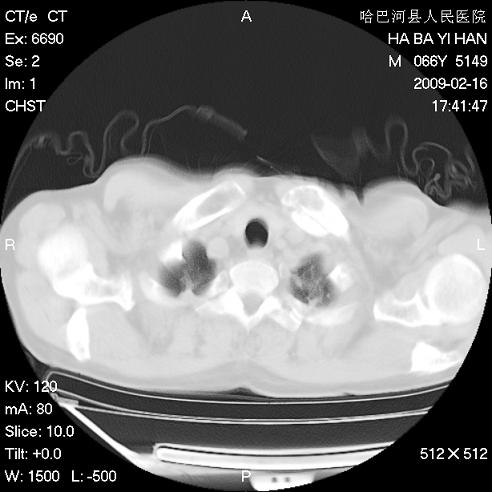

以下是引用huangxun4321在2009-2-16 20:18:00的发言:[br]部分病灶可见硬化边,部分可见骨质破坏消失,部分病灶内可见骨脊,说明病灶内既有良性病变,又有恶性病变,考虑骨巨细胞瘤恶变,未除骨纤恶变,畸形性骨炎少见,亦要考虑.

以下是引用731208在2009-2-16 20:31:00的发言:[br]考虑恶性胸膜间皮瘤并肋骨,脊柱转移。

以下是引用yijiansheng在2009-2-16 20:16:00的发言:[br]考虑恶性胸膜间皮瘤并肋骨,脊柱转移。

以下是引用形影不离在2009-2-16 19:55:00的发言:[br]考虑多发性转移瘤。